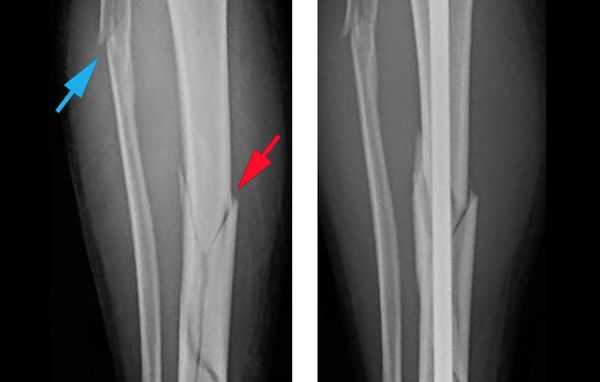

Объективно подтвердить диагноз позволяет рентгенологическое исследование голени в двух стандартных проекциях: прямой и боковой [8] . Чтобы избежать ошибок, рентген следует выполнять строго по стандартным укладкам.

В некоторых случаях, если требуется детальная диагностика нескольких сегментов голени или пациент находится в тяжёлом состоянии, показана компьютерная томография с 3d-реконструкцией кости. Исследование можно проводить и при вынужденном положении конечности, но такой томограф есть не во всех клиниках. Поэтому в некоторых случаях, если информации недостаточно, делаются уточняющие прицельные рентгеновские снимки отдельных сегментов кости.